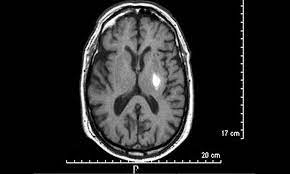

Los infartos lacunares son un tipo específico de infarto cerebral caracterizado por su tamaño reducido, generalmente inferior a 1.5 centímetros de diámetro. Estas lesiones se localizan principalmente en regiones del cerebro que reciben irrigación de arteriolas cortas penetrantes, tales como los ganglios basales, el puente de Varolio, el cerebelo, la cápsula interna y el tálamo. En menor frecuencia, también pueden presentarse en la sustancia blanca cerebral profunda.